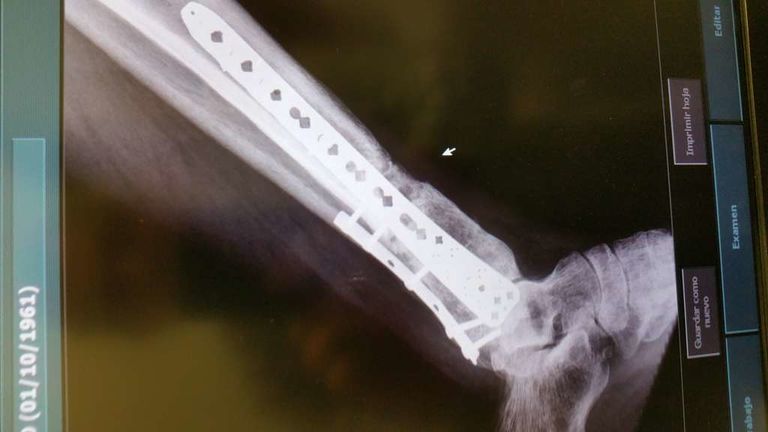

Mito Publicado 19 de Noviembre del 2014 Compartir Publicado 19 de Noviembre del 2014 Yo tuve un accidente de moto y me rompí la tibia y el peroné. Me tubieron que poner un clavo como el has puesto en las fotos y aún lo llevo, esto fue en el 2002 y ha dia de hoy no me molesta ni me lo voy a quitar. La rehavilitación fue muy muy lenta uffff y eterna. Estuve 3 meses sin poder poner el pie en el suelo, con muletas, la pierna se me quedó sin fuerza ninguna. En rehabilitación no notaba mejoría... creo recordar que pasó un año para que yo estuviera caminando normal. Me apunté a un gimnasio y ahí fue cuando recuperé toda la fuerza. Mucha paciencia y echarle muchas ganas de recuperación y siento mucho lo que te ha pasado, por que es superdoloroso y muy pesado -sombrero Enlace al comentario Compartir en otros sitios web More sharing options...

SuperGabaDink Publicado 19 de Noviembre del 2014 Compartir Publicado 19 de Noviembre del 2014 Mucho animo y paciencia compi! Me sumo a Mito ya que me paso algo parecido aunque tarde un poco mas...Una buena rehabilitación sumada a la que le eches tu aparte es la clave. A eso sumale una buena dosis de animo y positivismo pensando que te pondras bien aunque el proceso sea lento, y ya sera historia pasada. Yo me rompi tambien tibia y perone al caerme el scooter encima de mi pierna. La tibia en 3 cachos,desplazada,astillada etc...casi pierdo la pata. Llevaba mas hierros que Robocop y un sin fin de operaciones con injertos variados..jejeje; tarde 2 años en recuperarme,3 en olvidarme del tema y no cojear y 4 en poder volver a poner mi culo en una moto... No te desanimes,ya veras como en nada podras darle gas de nuevo. Enlace al comentario Compartir en otros sitios web More sharing options...

jerolo Publicado 13 de Diciembre del 2015 Autor Compartir Publicado 13 de Diciembre del 2015 Hola,pues si el post fue de Noviembre del año pasado pues llevo 2 operaciones más-van cinco-y otros 2 injertos al fin el hueso empieza a hacer callo,pero aún falta,y me quedo cojo Enlace al comentario Compartir en otros sitios web More sharing options...

jerolo Publicado 31 de Enero del 2016 Autor Compartir Publicado 31 de Enero del 2016 El lunes 1 placa y a ver como va la cosa,subiré foto PD. Cómo me duele la puta pierna :-) Enlace al comentario Compartir en otros sitios web More sharing options...